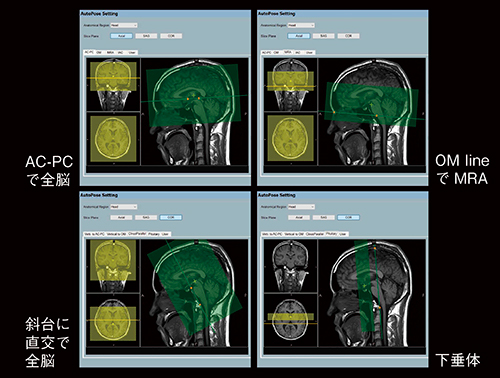

頭部検査では,T1強調画像やT2強調画像といった通常の全脳撮像のほかに,MRAなど通常の全脳撮像とは異なる角度や撮像範囲のタスクが混在します。ECHELON Smart Plusに搭載された新たなAutoPoseは,撮像断面の角度や範囲のパターンを事前に最大5断面まで設定しておくことができます(図6)。したがって,撮像断面や撮像範囲が異なるタスクが混在するプロトコールにおいても,それぞれに自動的に位置決めを行い,自動的に検査を進めることが可能です。

図6 AutoPoseの多彩なプリセット例